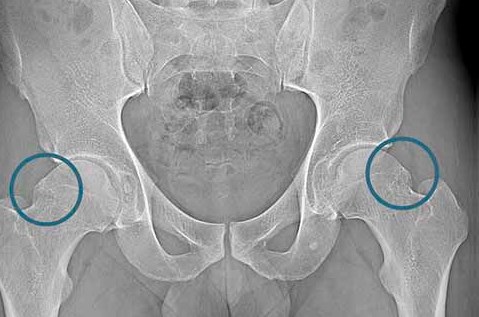

Złamanie szyjki kości udowej to uraz w obrębie stawu biodrowego, który po upadku uniemożliwia obciążenie nogi i powoduje silny ból w pachwinie lub biodrze. Dotyczy osób starszych z osteoporozą, a u młodszych jest skutkiem urazu wysokoenergetycznego. Złamanie powstaje w szyjce łączącej głowę kości udowej z trzonem i leży wewnątrz torebki stawowej. Zaburza dopływ krwi do głowy kości udowej i zwiększa...